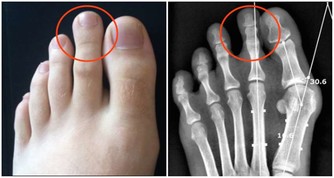

股骨頭壞死是導致胯骨疼痛的一個重要原因,發生率約佔胯骨疼痛的20%。它是指股骨頭骨細胞因血液供應不足而逐漸死亡,最終導致骨頭結構損壞的一種病理過程。

股骨頭壞死可分為特發性和繼發性兩大類。

特發性較多見,主要與個體血液供應不良等先天因素相關。繼發性則常由創傷、使用荷爾蒙、酗酒等導致。無論何種原因,都會使骨頭微循環阻塞,造成局部缺血壞死。

病程初期可出現活動後疼痛,休息後緩解。隨著壞死面擴大,胯部疼痛會加劇,持續壓痛,休息後不會緩解,嚴重影響生活。透過檢查可見X光股骨頭密度降低、塌陷。對於這種疾病的治療,專家建議以保守治療為主,也可依年齡選擇人工關節置換。

而預防股骨頭壞死的關鍵在於確保股骨頭的良好血液供應。中老年人應多進行適度運動,增強心肺功能,並控制脂肪肝等。同時避免外傷,不濫用藥物和酒精。另外,發現早期症狀,及時治療也很關鍵。要知道,股骨頭壞死若處理不當,最終可使髖關節功能完全喪失。